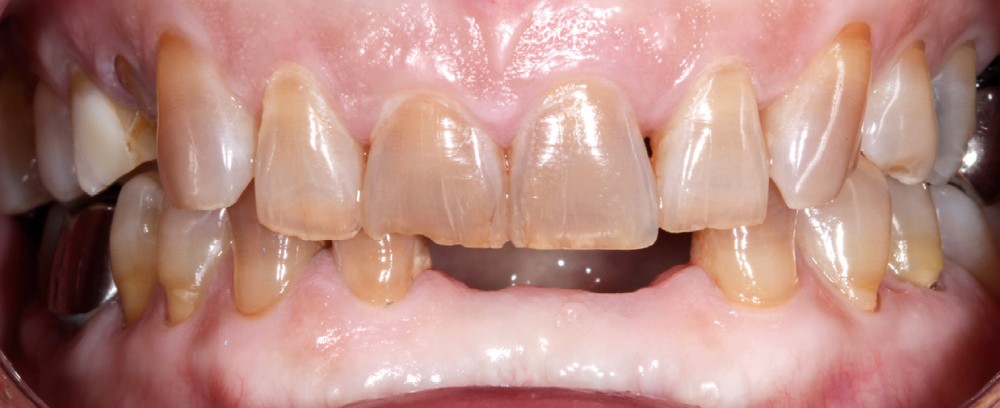

– Traumatismes (fig. 5a, b).